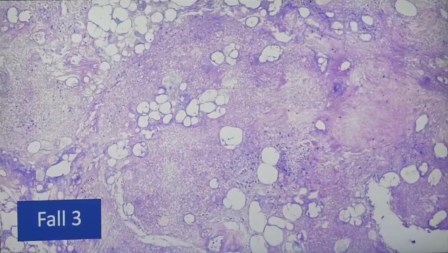

Páncreas y otros órganos

Necrosis de páncreas con infiltración de linfocitos

Vaso con infiltración de linfocitos

Brónculo-folículo, esto suele verse en enfermedades autoinmunes crónicas, pero no debería ser en pacientes con pulmones normales.

Folículo de linfoma con dos focos que tienen mucha fuerza. Se ven focos de infección que se ven en los de la memoria y los que causan la respuesta del sistema inmunitario

Infiltración de linfocitos en el hígado, suele pasar en hepatitis, pero es poco probable en casos vasculares. Para que el hígado tenga un nudo tan delimitado, que no es una angiopatitis, sino un folículo parte de un linfoma

Nodo linfático de casi cuatro centímetros, fuerte reacción inmune, linfoma

Los folículos del nódulo linfático